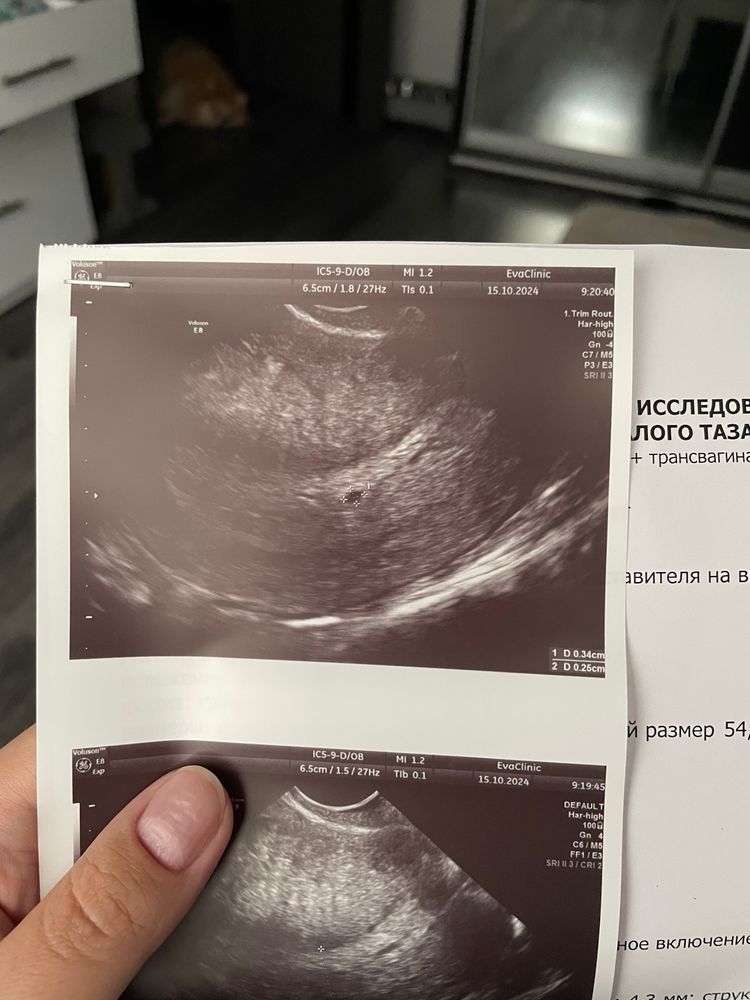

Это ПЯ?

Да,это малюсенькое ПЯ..ходила на узи в 4 недели и было такое же..через 2,5 недели уже был маленький эмбриончик и сердечко..сейчас уже ждем первый скрининг🫶 Не переживайте,всё у вас хорошо))

Да, похоже что ПЯ, но очень маленькое 🥰как раз через недельку вырастет и поставят точный срок Б

Лидия, у меня в пятницу 27 сентября при хгч 2500 было видно ПЯ под вопросом,около 2мм но очень плохо видно, сдала хгч 28 числа 29 было 5524 я пошла в понедельник уже 1 октября к другому узисту и поставили срок 4 недельки и размер ПЯ уже был 4мм...14 была на узи уже видно эмбриончик но пока не слышно сердечко,на следующей неделе только❤

Такой эндометрий малюсенький

Диана, почему? даже большеват